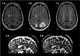

Marchiafava–Bignami disease is a progressive neurological disease of alcoholism, characterized by corpus callosum demyelination and necrosis and subsequent atrophy. The disease was first described in 1903 by the Italian pathologists Amico Bignami and Ettore Marchiafava in an Italian Chianti drinker. [Source: Wikipedia ]